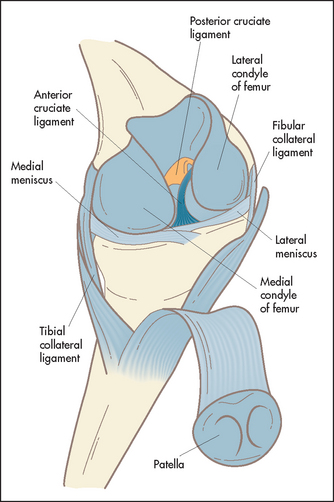

The knee is a complex hinge joint formed by the distal femur, the patella and the proximal end of the tibia (see Figure 24.32). The bones are enclosed in a joint capsule with an extensive synovial membrane. Lateral stability is provided by the lateral collateral ligaments, and antero-posterior movement is restricted by the cruciate ligaments. There is extensive articular cartilage that acts as a shock absorber and allows smooth gliding movements between the ends of the bones.

Test the ligaments next (see Good signs guide 24.1). The lateral and medial collateral ligaments are assessed by having the knee slightly flexed while holding the leg, with your forearm resting along the length of the tibia; lateral and medial movements of the leg on the knee joint are tested (see Figure 24.34(b)). Meanwhile steady the thigh with your other hand. Movements of more than 5–10° are abnormal. The cruciate ligaments (Figure 24.34(c)) are tested next. Steady the patient’s foot with your elbow or by sitting on it. Flex the patient’s knee to 90°. Grasp the tibia and attempt anterior and posterior movements of the leg on the knee joint. Movement may be detected by your thumbs positioned at the joint margins. Again, movement of more than 5–10° is abnormal. Increased anterior movement suggests anterior cruciate ligamentous laxity, and increased posterior movement suggests posterior cruciate ligamentous laxity. The Lachman test may be more accurate (LR+ 42.0, LR– 0.1).9 Here the knee is flexed 20–30° while the patient is lying supine. Grasp the femur (place your hand above the knee) to steady it, then grab the lower leg below the knee and give it a quick forward tug. It is abnormal when there is exaggerated anterior tibial movement or the knee fails to stop with a thud.